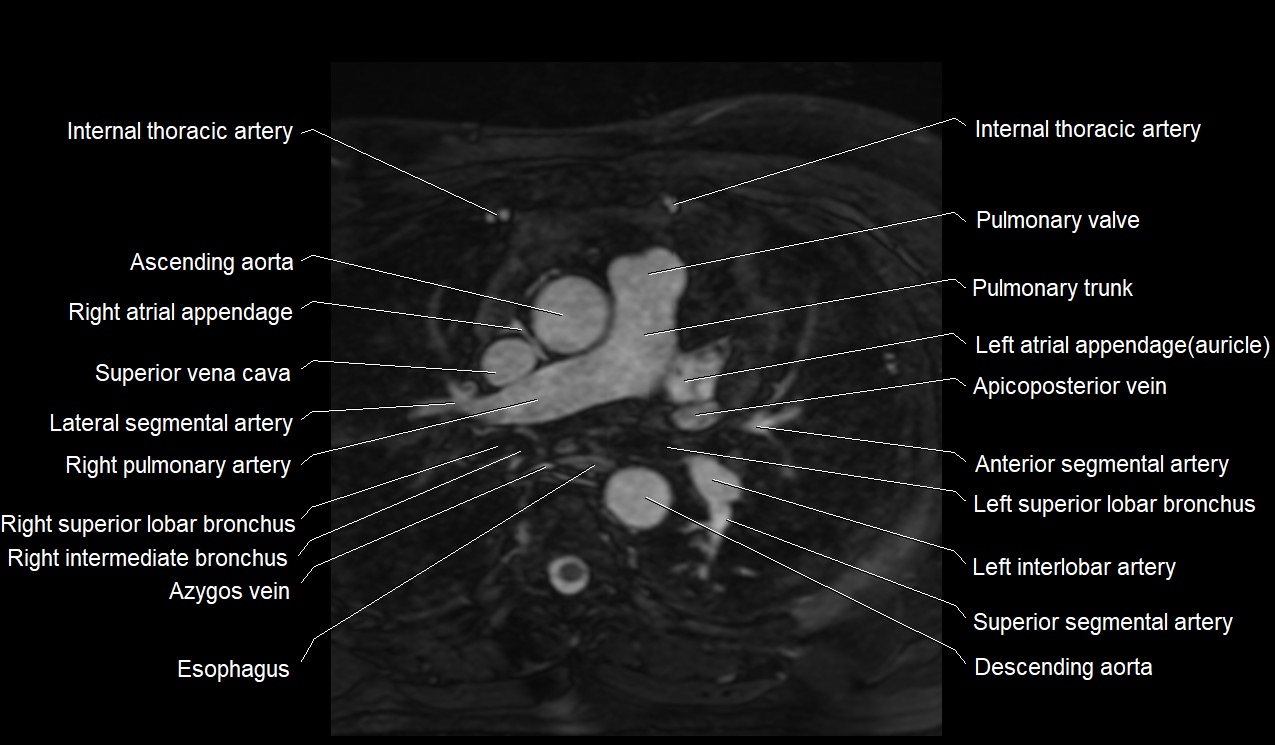

MRI image